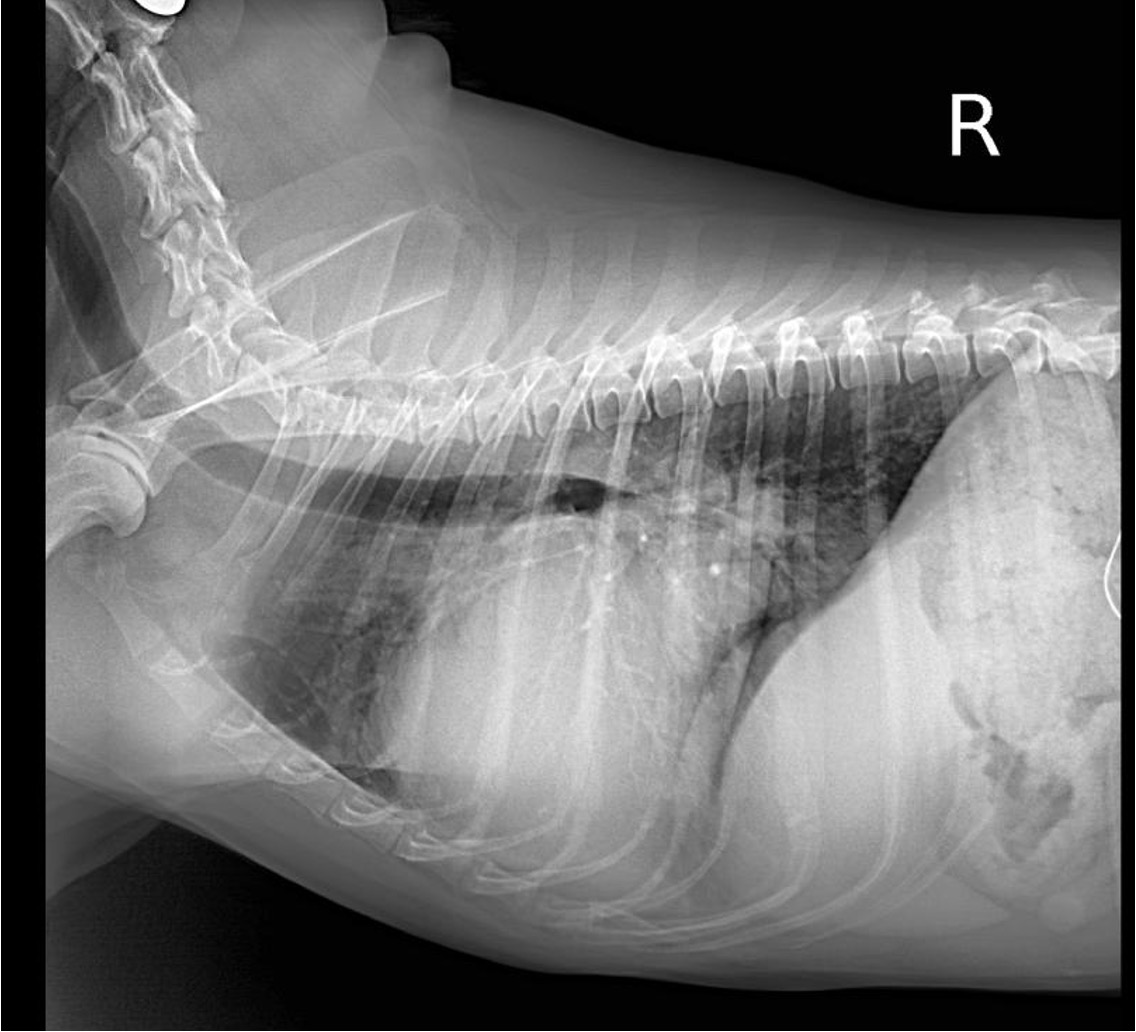

La radiografía de tórax y el TAC, ¿Cómo sacarles el mejor partido?

¿Y cómo la evaluamos en la clínica?

Se evalúa principalmente con ecocardiografía:

Flujo transmitral (Doppler pulsado): relación E/A, tiempo de desaceleración.

Haz clic en la imagen para obtener una vista más ampliada

Doppler tisular (TDI): onda e’ (relajación) y E/e’ (estimación de presiones de llenado).

Aurícula izquierda (LA/Ao): refleja cronicidad de la sobrecarga.

Flujo venoso pulmonar (si es posible).

En la disfunción diastólica, el problema está en el llenado ventricular alterado debid

o a rigidez y/o alteraciones estructurales. Y su principal signo clínico es la congestión a nivel pulmonar (si el problema es izquierdo) o abdominal (ascitis) si es del lado derecho.